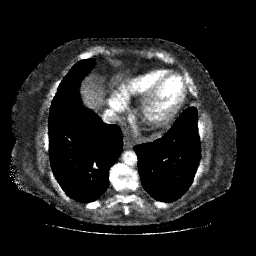

Targeted Slice 70 - Mediastinum Window Analysis (Generated vs Real Venous)

0.692

Mediastinum SSIM

39.4

Mediastinum RMSE

17.2

Mediastinum MAE

Average Mediastinum Window Metrics Across All Slices (101 slices) - Generated vs Real Venous

0.673

Mediastinum SSIM (Avg)

41.7

Mediastinum RMSE (Avg)

19.0

Mediastinum MAE (Avg)